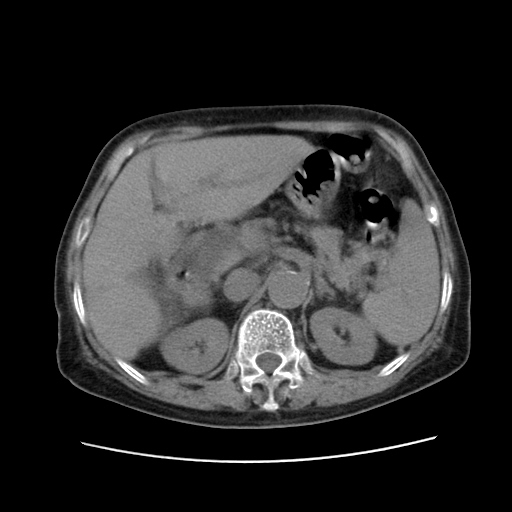

女,77.无不适

肝脏变异、异位胆囊,肝右叶肝内胆管结石并肝内胆管扩张。

肝右叶肝内胆管结石并肝内胆管扩张。

肝右叶肝内胆管结石并肝内胆管扩张

胆总管扩张

肝右叶肝内胆管结石并肝内胆管扩张。胆总管下段梗阻,考虑壶腹部占位。

右侧肝内胆管局限性扩张,其内密度不均匀,扩张的胆管壁增厚,考虑肝内胆管炎合并结石可能性大

肝右叶肝内胆管结石并肝内胆管扩张。胆总管下段梗阻,考虑壶腹部占位。支持